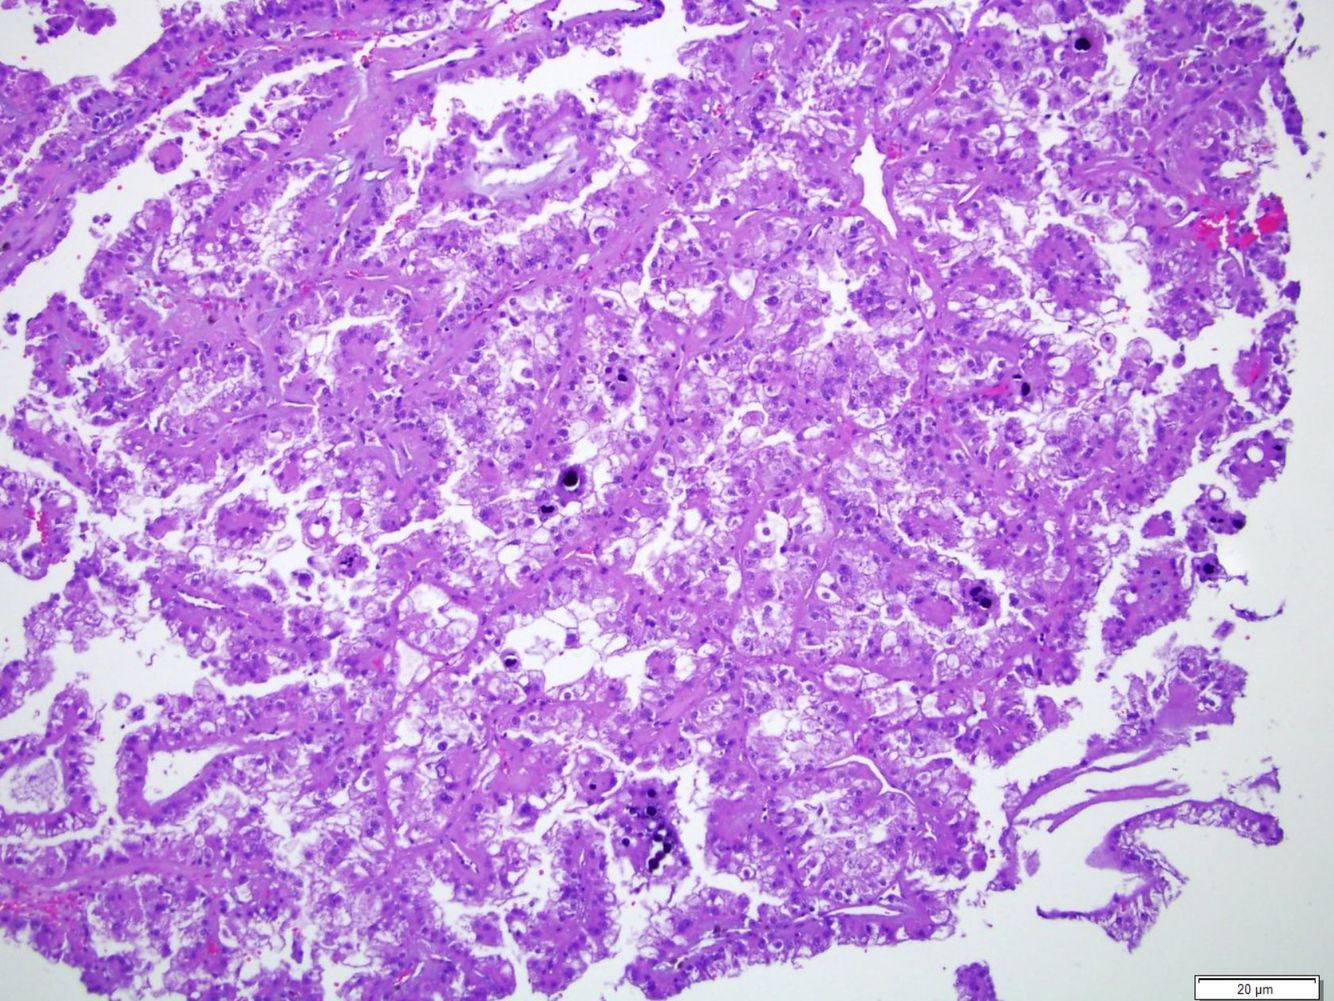

Acquired cystic kidney disease-associated renal cell carcinoma

Found in end-stage kidneys. An unmistakable grungy mix of oncocytic cells and bubbly, microcystic architecture with hemorrhage, necrosis, and oxalate crystals.

The abundant oxalate crystals are a dead giveaway, if nothing else clues you in.